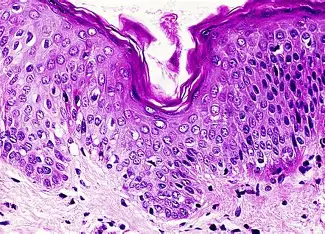

Which kind of tissue is shown?

Skin